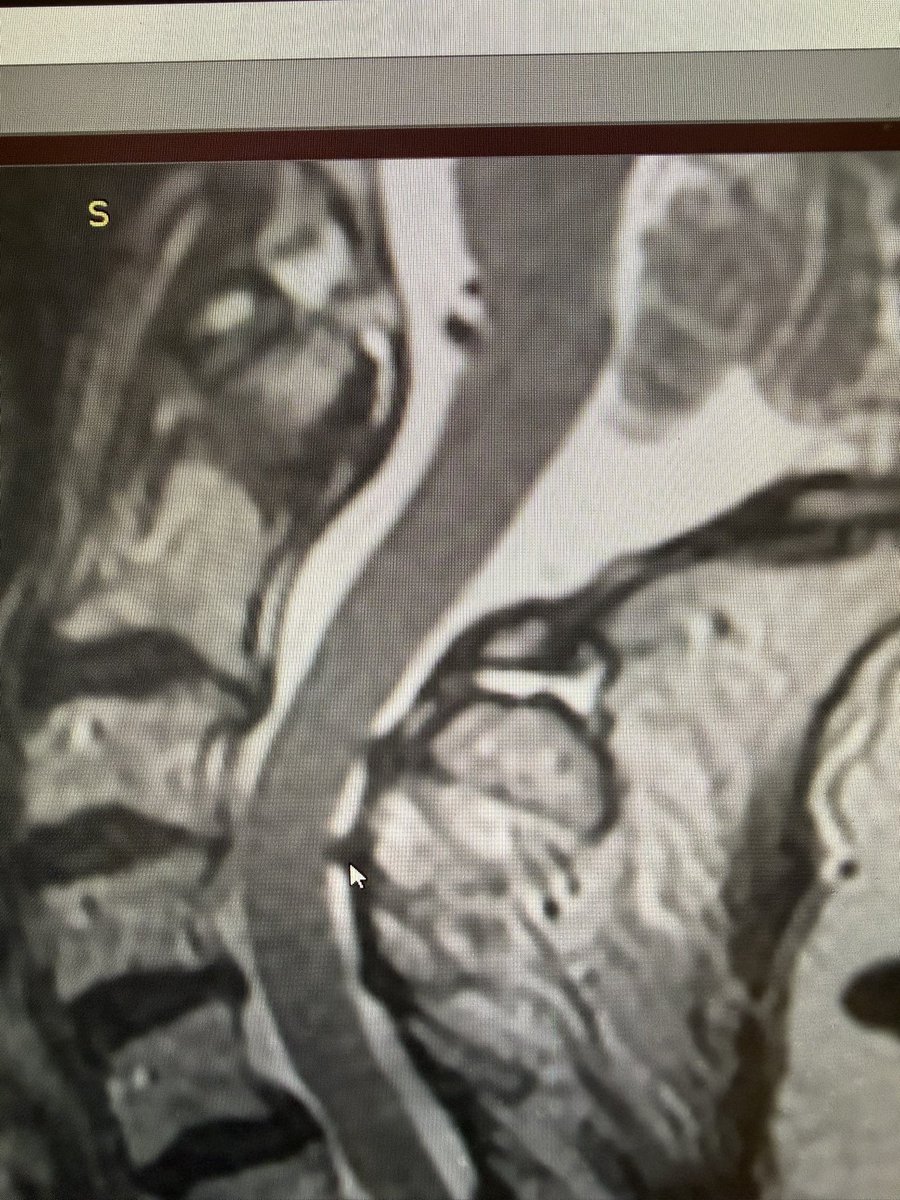

Douglas Beall@dougbeall·

Radiologists: please be sure to mention autofusions on cross-sectional imaging studies. This typically indicates a seronegative spondyloarthropathy. That was the case in this patient with neck pain but no mention on the radiology report.

Douglas Beall tweet mediaDouglas Beall tweet mediaDouglas Beall tweet mediaDouglas Beall tweet media